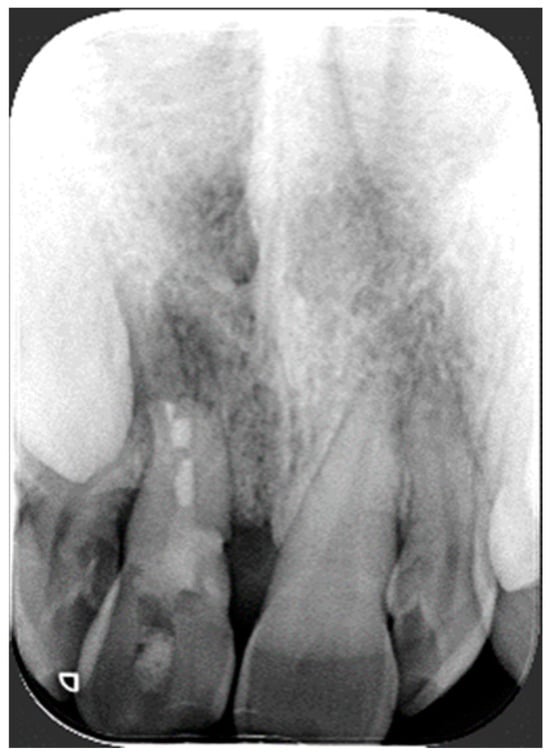

2. Case Report